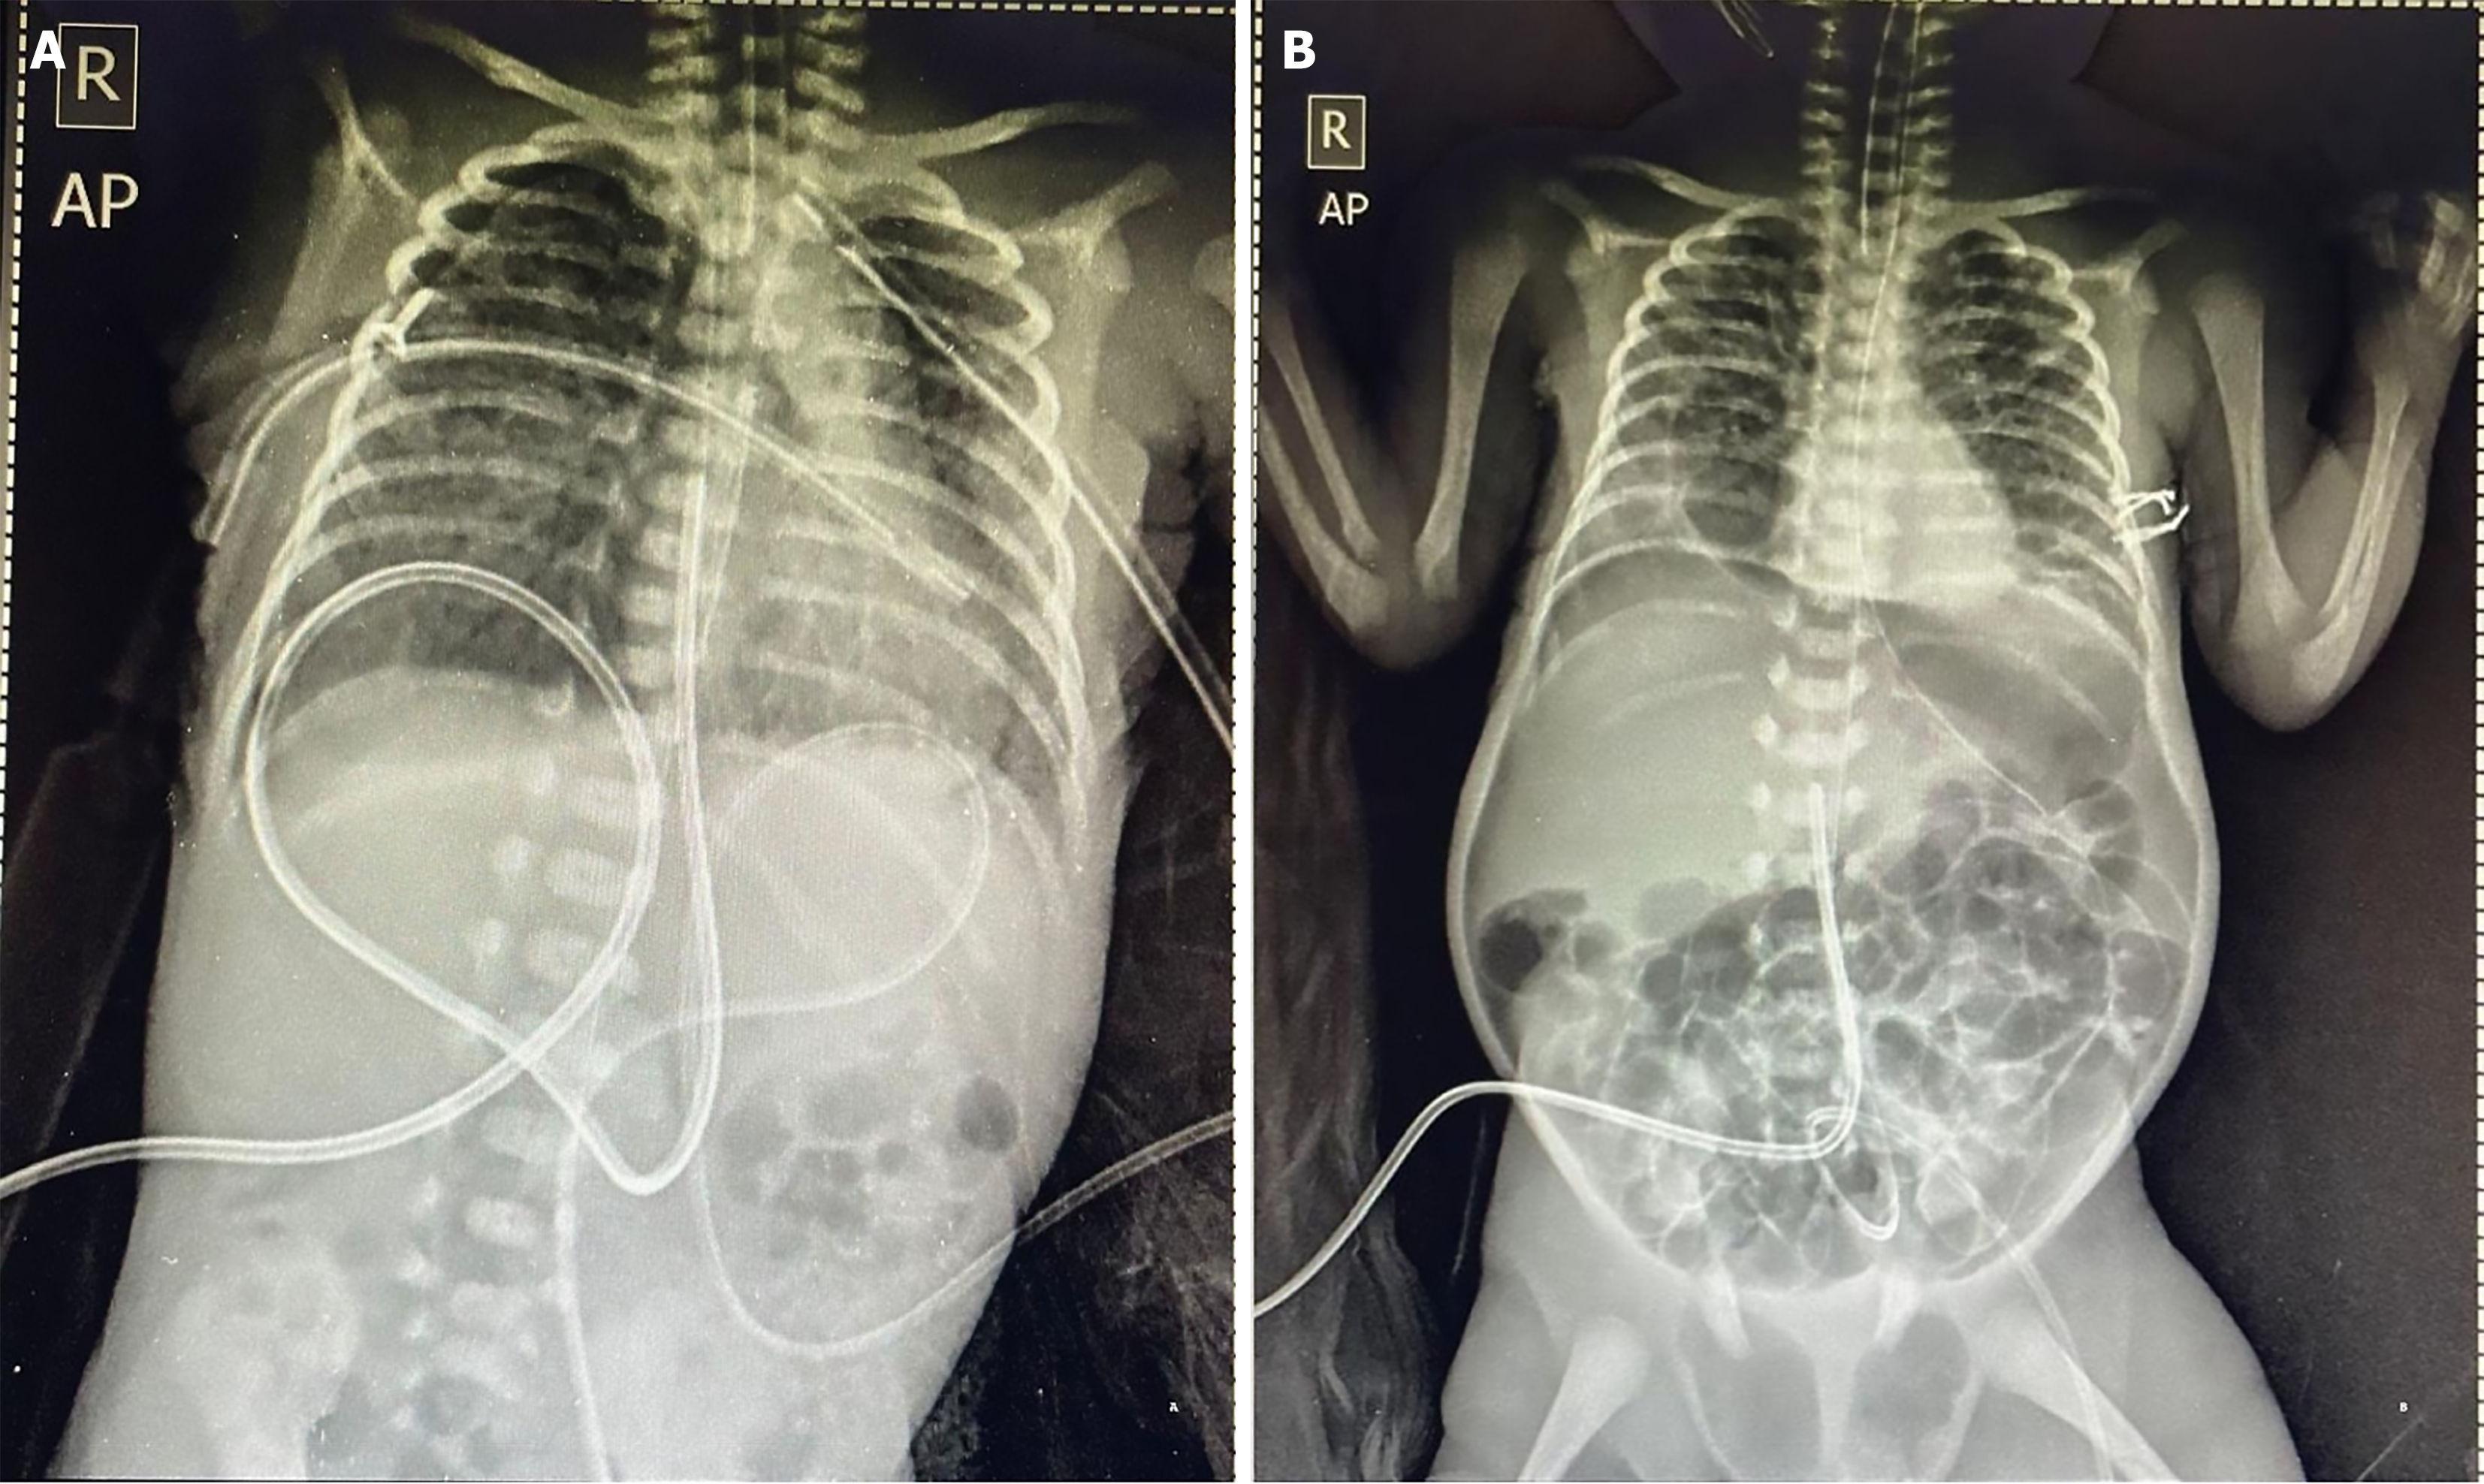

Figure 1 Abdominal radiograph.

A: Chest and abdominal radiograph (anteroposterior view) obtained on the first day of life, demonstrating the central position of the umbilical venous catheter; B: Chest and abdominal radiograph (anteroposterior view) obtained on the seventh day of life, demonstrating the penumoperitoneum (football sign) and position of the umbilical venous catheter.